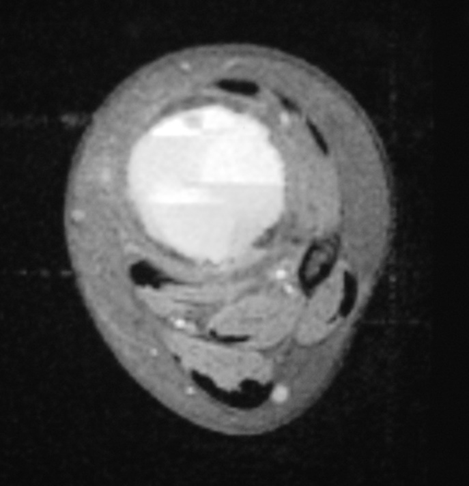

MRI

- Geographic well circumscribed

- High signal on T2 weighted MRI images

- Fluid/Fluid level (T2) are highly characteristic

Fig 2 a-e. MRI of an ABC of Distal Tibia: Fig 2 a-c: geographic cystic expansile lesion with fluid-fluid levels. The fluid-fluid levels are caused by bleeding into the cavities. The blood collects and the degredation products settle to the gravity dependent areas of the cavities. This shows up as fluid-fluid levels on the MRI. Fig 2 d,e: This is a gadolinium enhanced MRI of the ABC of the distal tibia. There is peripheral and septal enhancement indication cyst formation. The contrast outlines the cystic cavities but does not enter into the center